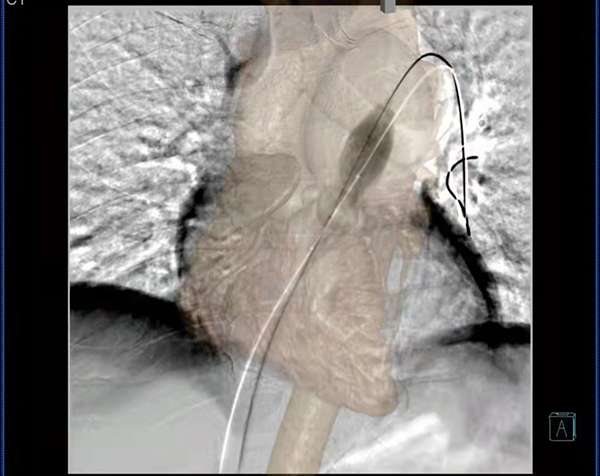

此次在心臟外科進行的肺動脈瓣閉式擴張術中,放射科技師成功運用CTA與3D-DSA影像融合技術,將患者術前肺動脈CTA薄層影像與胸部3D-DSA影像進行融合得到肺動脈的三維路徑,通過旋轉(zhuǎn)融合的三維路徑來為術者提供參考,選擇最佳的造影角度建立手術入路,引導導絲通過建立的手術入路從右心室進入肺動脈,從而達到擴張肺動脈瓣的目的。